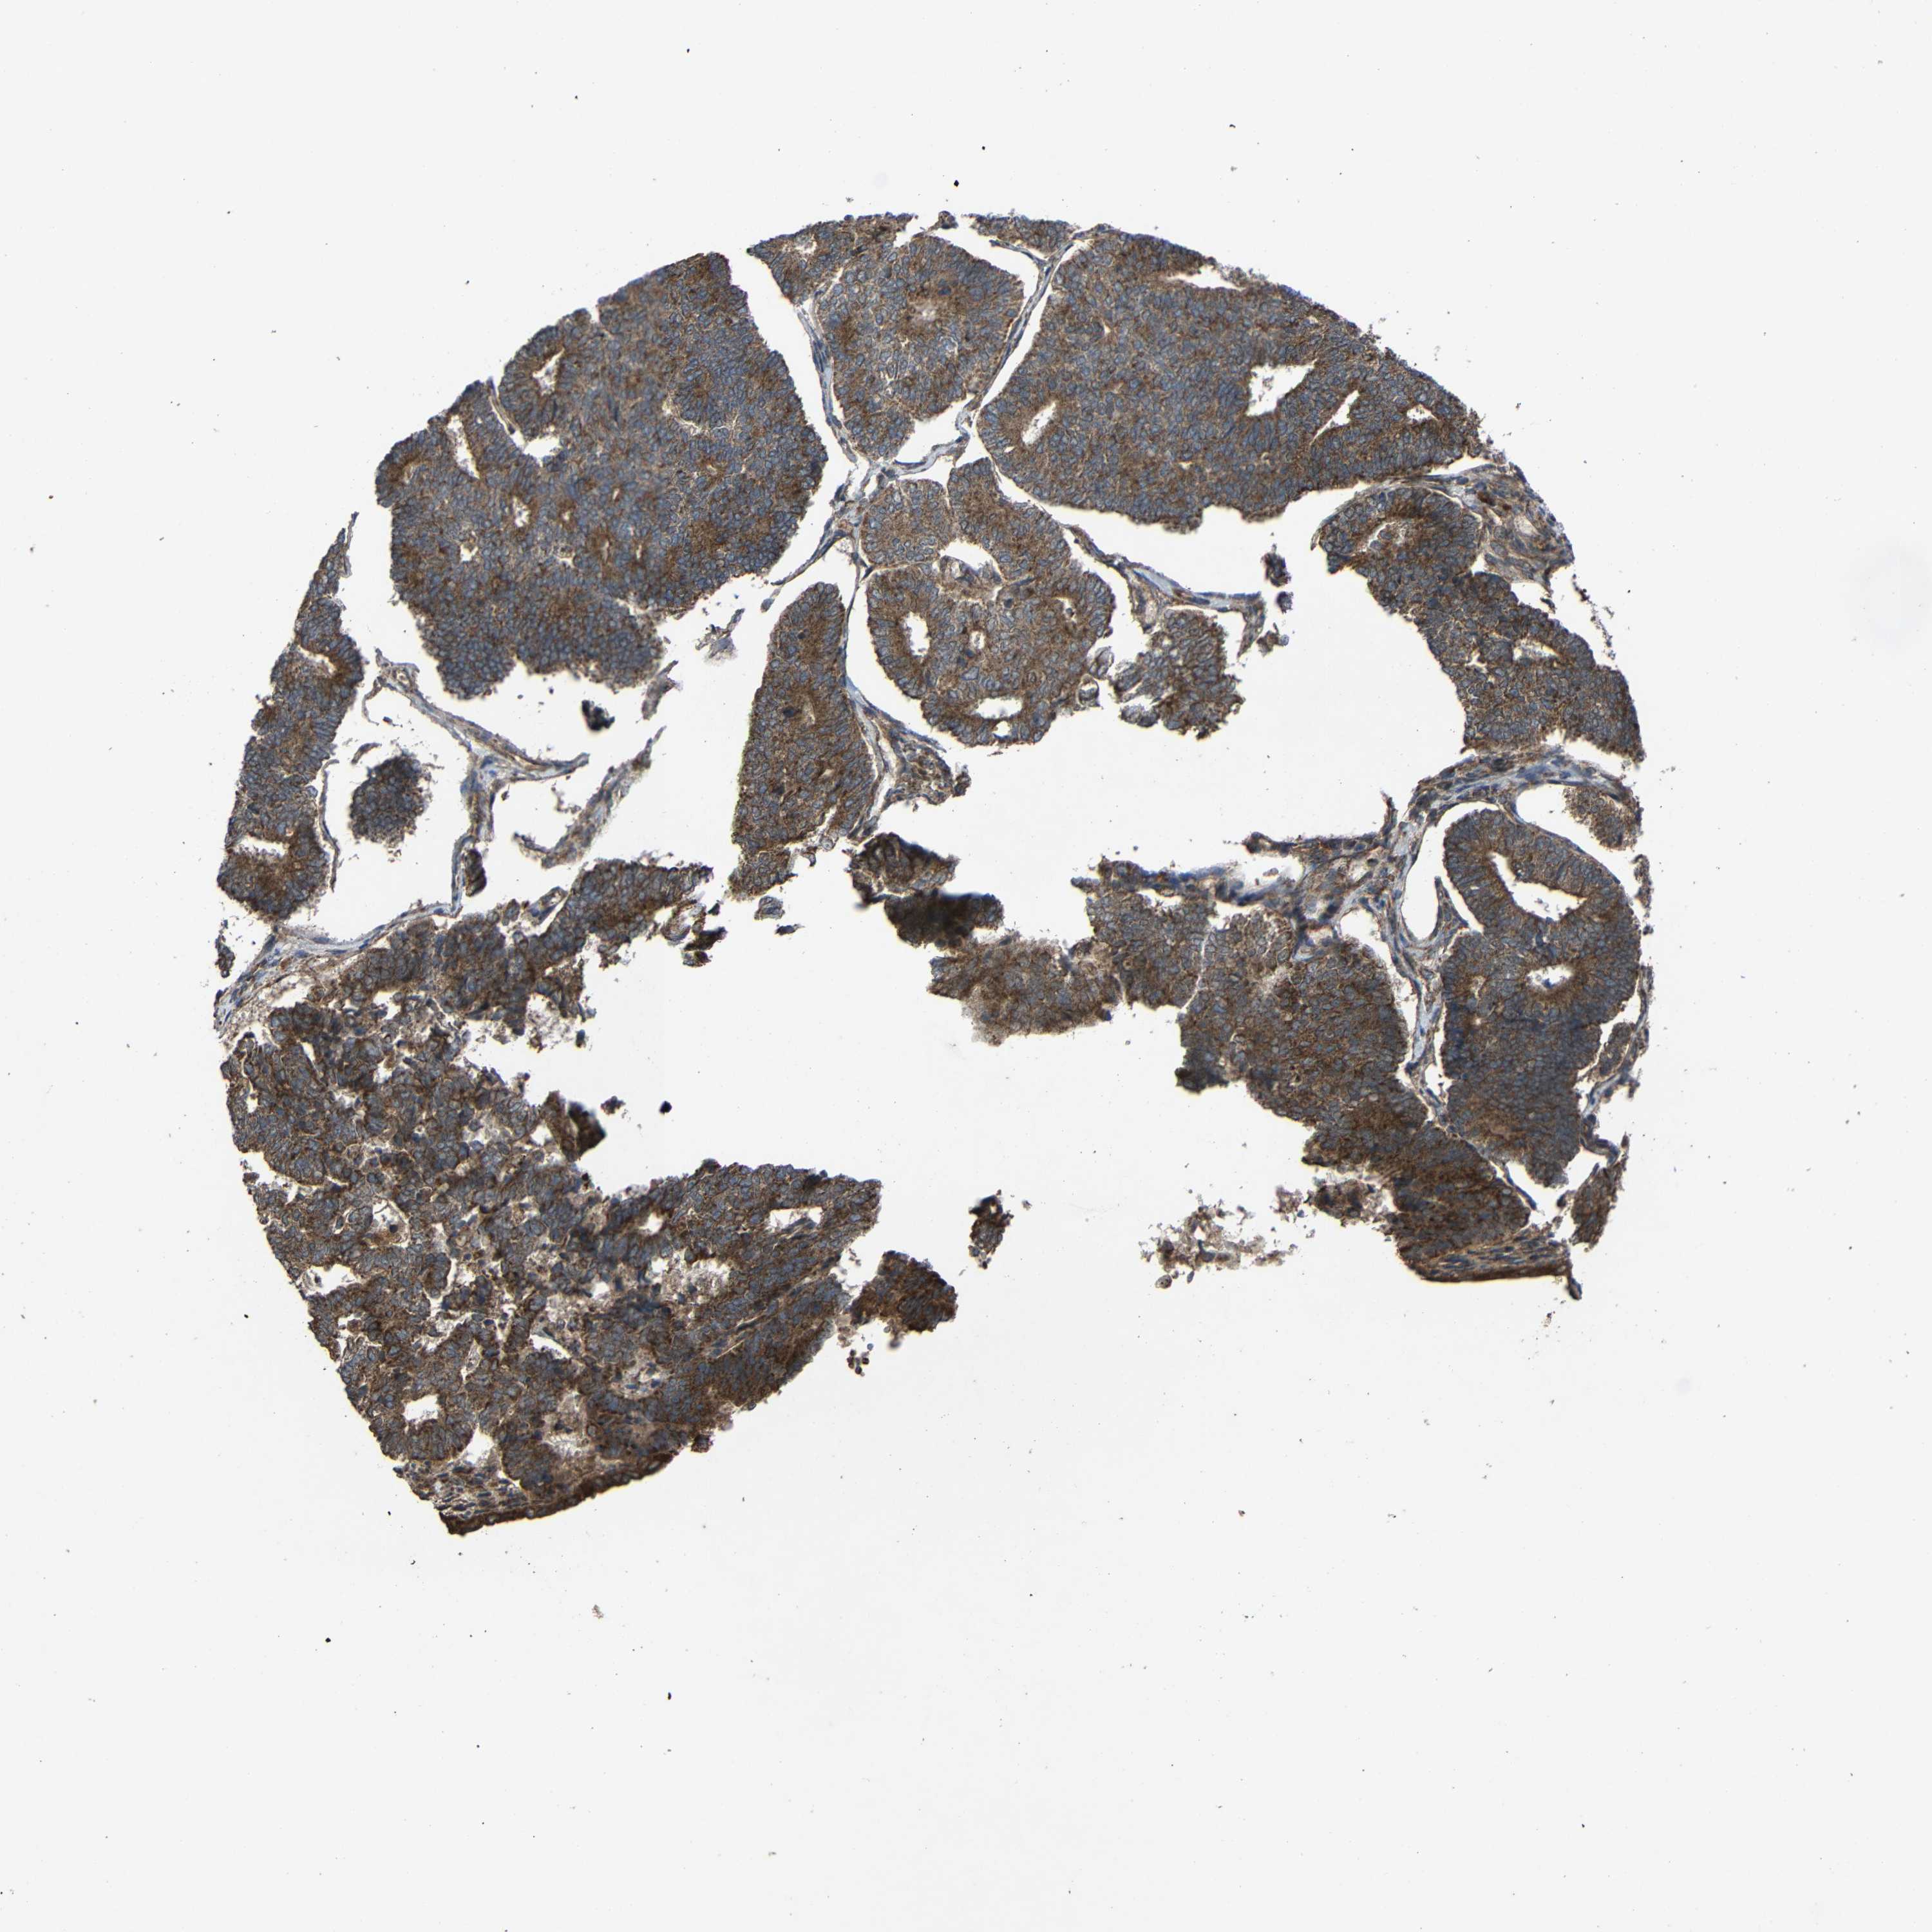

ENDOMETRIAL CANCER - Protein expressioni

A mouse-over function shows sample information and annotation data. Click on an image to view it in a full screen mode. Samples can be filtered based on level of antibody staining by selecting one or several of the following categories: high, medium, low and not detected. The assay and annotation is described here.

Note that samples used for immunohistochemistry by the Human Protein Atlas do not correspond to samples in the TCGA dataset.

Antibody stainingi

Antibody staining in the annotated cell types in the current human tissue is reported as not detected, low, medium, or high, based on conventional immunohistochemistry profiling in selected tissues. This score is based on the combination of the staining intensity and fraction of stained cells.

Each image is clickable and will lead to virtual microscopy that enables deeper exploration of all samples and also displays staining intensity scores, fraction scores and subcellular localization as well as patient and tissue information for each sample.

Antibody HPA011294

Antibody HPA012819

Staining

High

Medium

Low

Not detected

Intensity

Strong

Moderate

Weak

Negative

Quantity

>75%

75%-25%

<25%

None

Location

Nuclear

Cytoplasmic/membranous

Cytoplasmic/membranous,nuclear

Adenocarcinoma, NOS